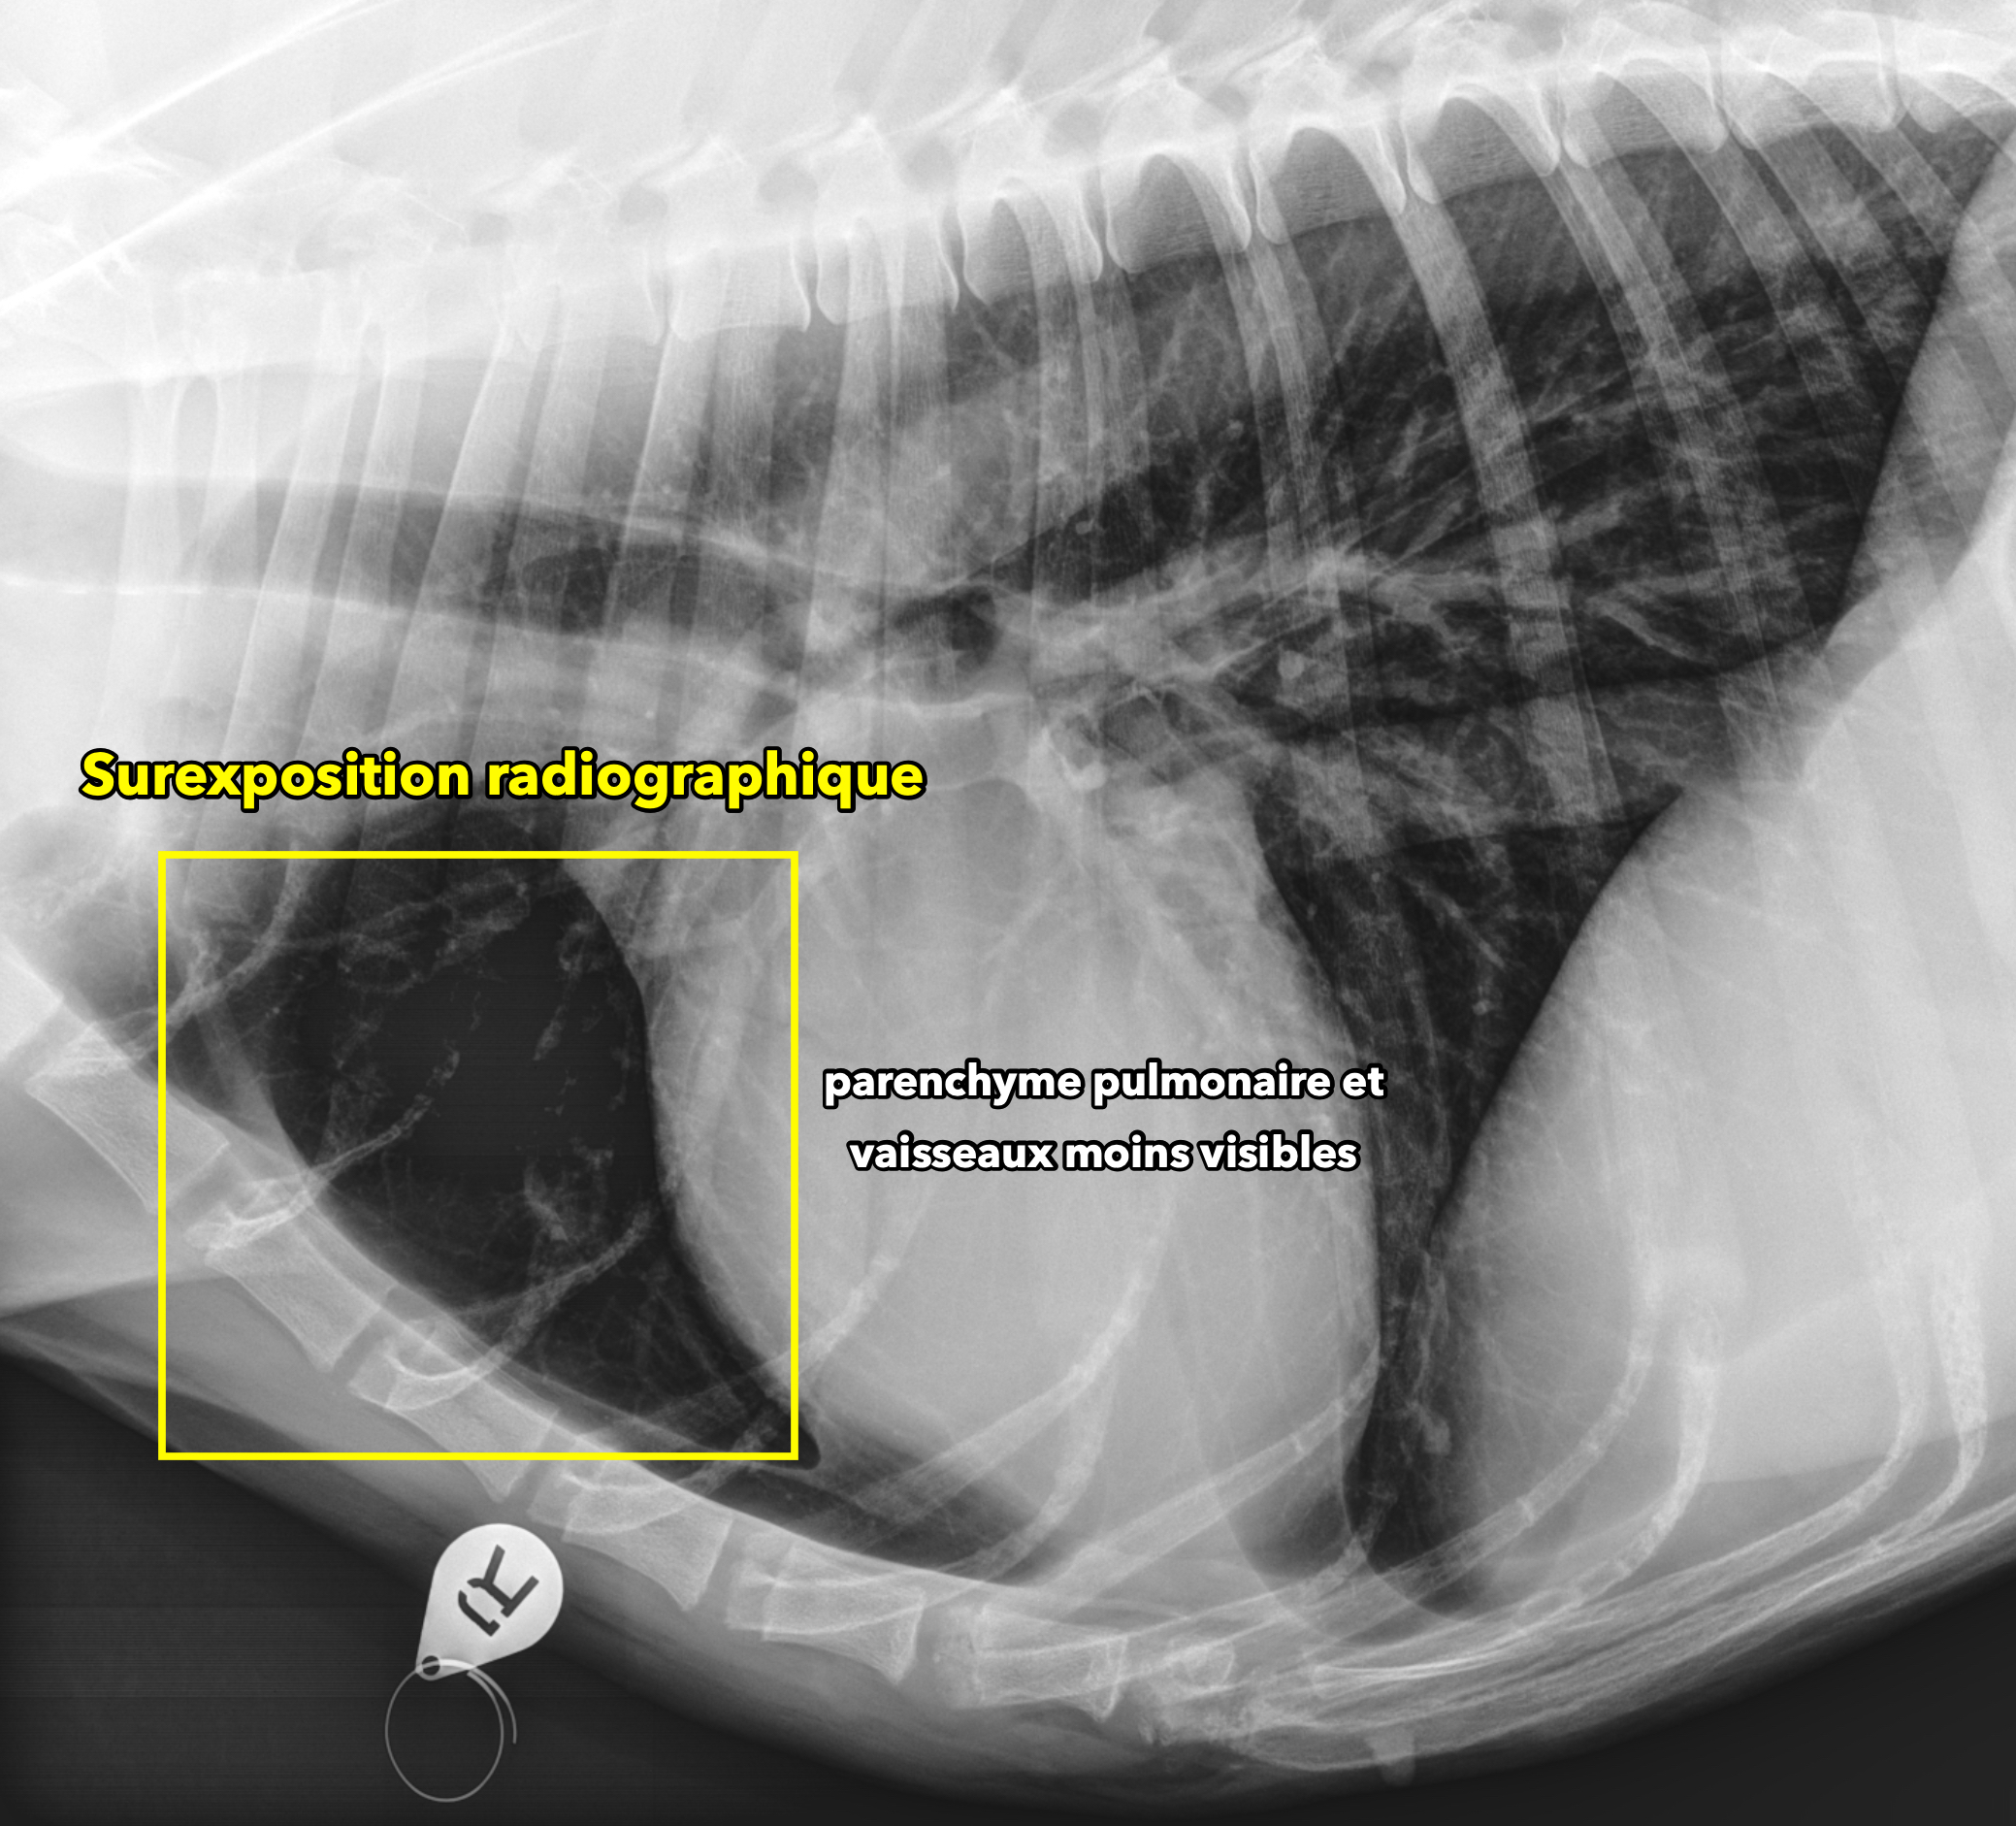

qualitecc81-5_radio-surexposecc81e